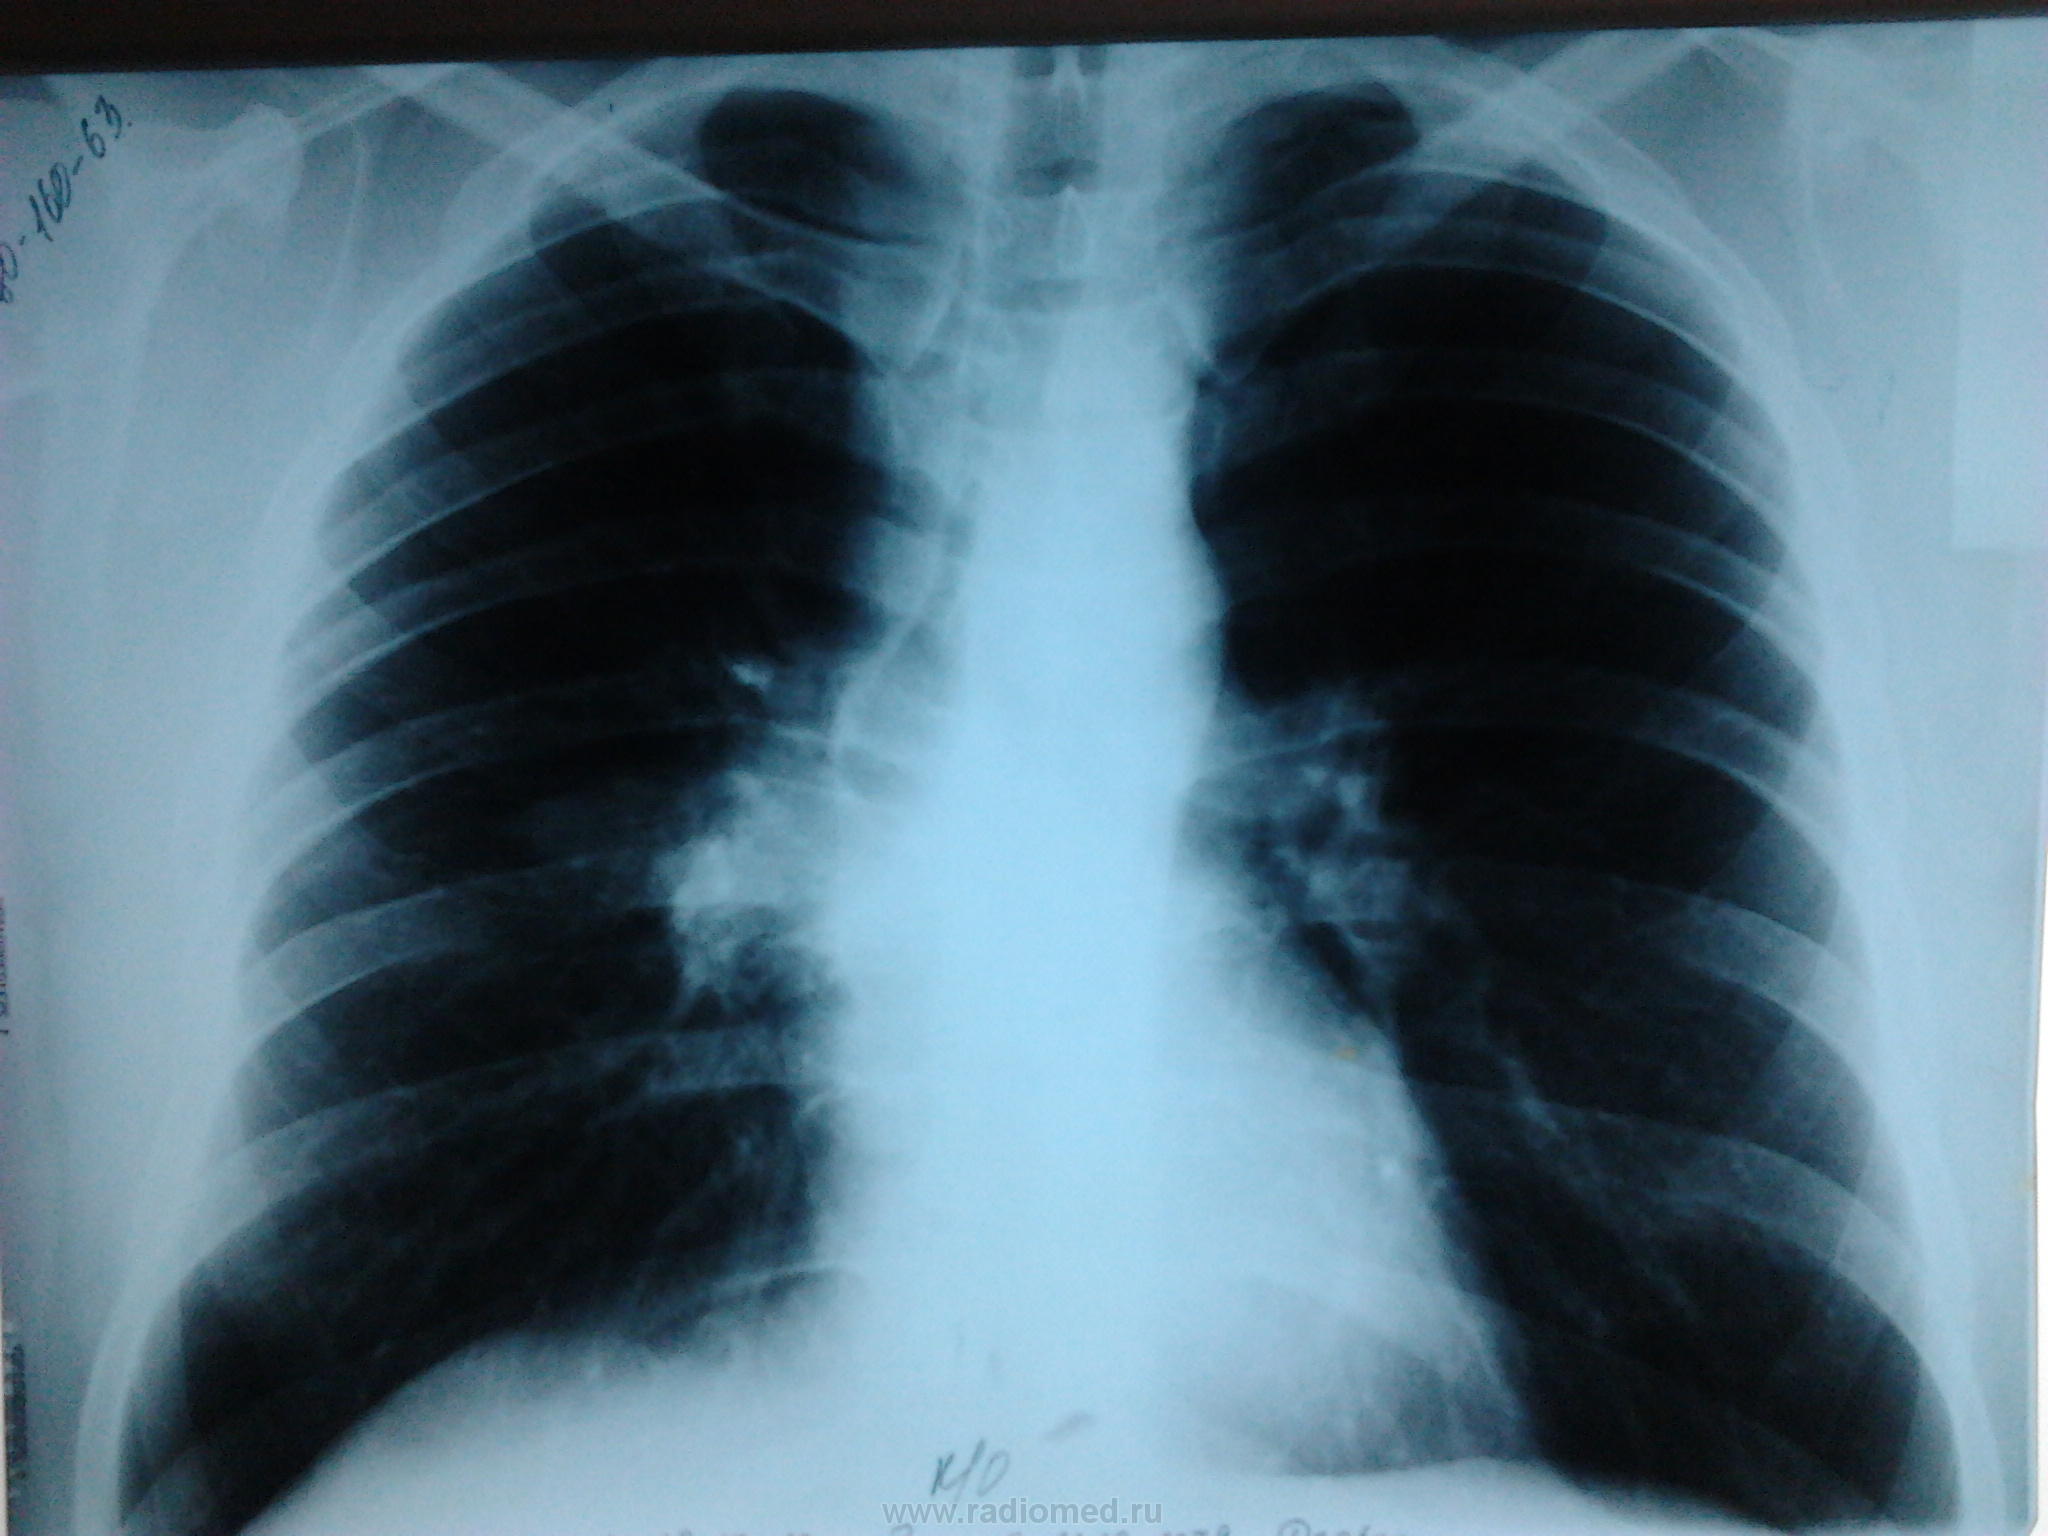

Великолепные томограммы в боковой проекции с отчётливой картиной поражения 6 сегментарного бронха.

[/ Ее я тоже исключала . Но почувствовала неладное в S6-посмотрите внимательно,-в его основании -тень некрупного отграниченного инфильтрата с распадом. На обзорном снимке-в прикорневой зоне -участок инфильтрации, вот и выясняла, что ж это такое. Написала,что процесс "наш", а дальше-дело техники. В результате (была и ФБС )-туберкулома с распадом. И туберкулез сегментарного бронха S6. И туберкулез ВГЛУ.Предвижу вопрос-не ВИЧ, в том-то и дело. Необычно,но бывает.

Алкс! Спасибо за совет,но снимки "пожестче"специально "заказала",чтобы "пробить" л/у и бронхи посмотреть. Именно так и обнаружила туберкулому с распадом (для Nkolas'а).А щипцовая ФБС была под контролем экрана, т.е. моим,-там тоже видно было,что распад.Результат гистологии тоже подтвердил то,что уже и так было видно.Про ВИЧ ведь специально написала-см.выше в посте N 14. И поэтому тоже необычно. Да,Сергей! Зря,наверное,так рано опубликовала результат. Надо было Вас всех подождать. Потомить еще. В следующий раз тогда уж. Еще случаи будут, не переживайте.

это ателеказ.